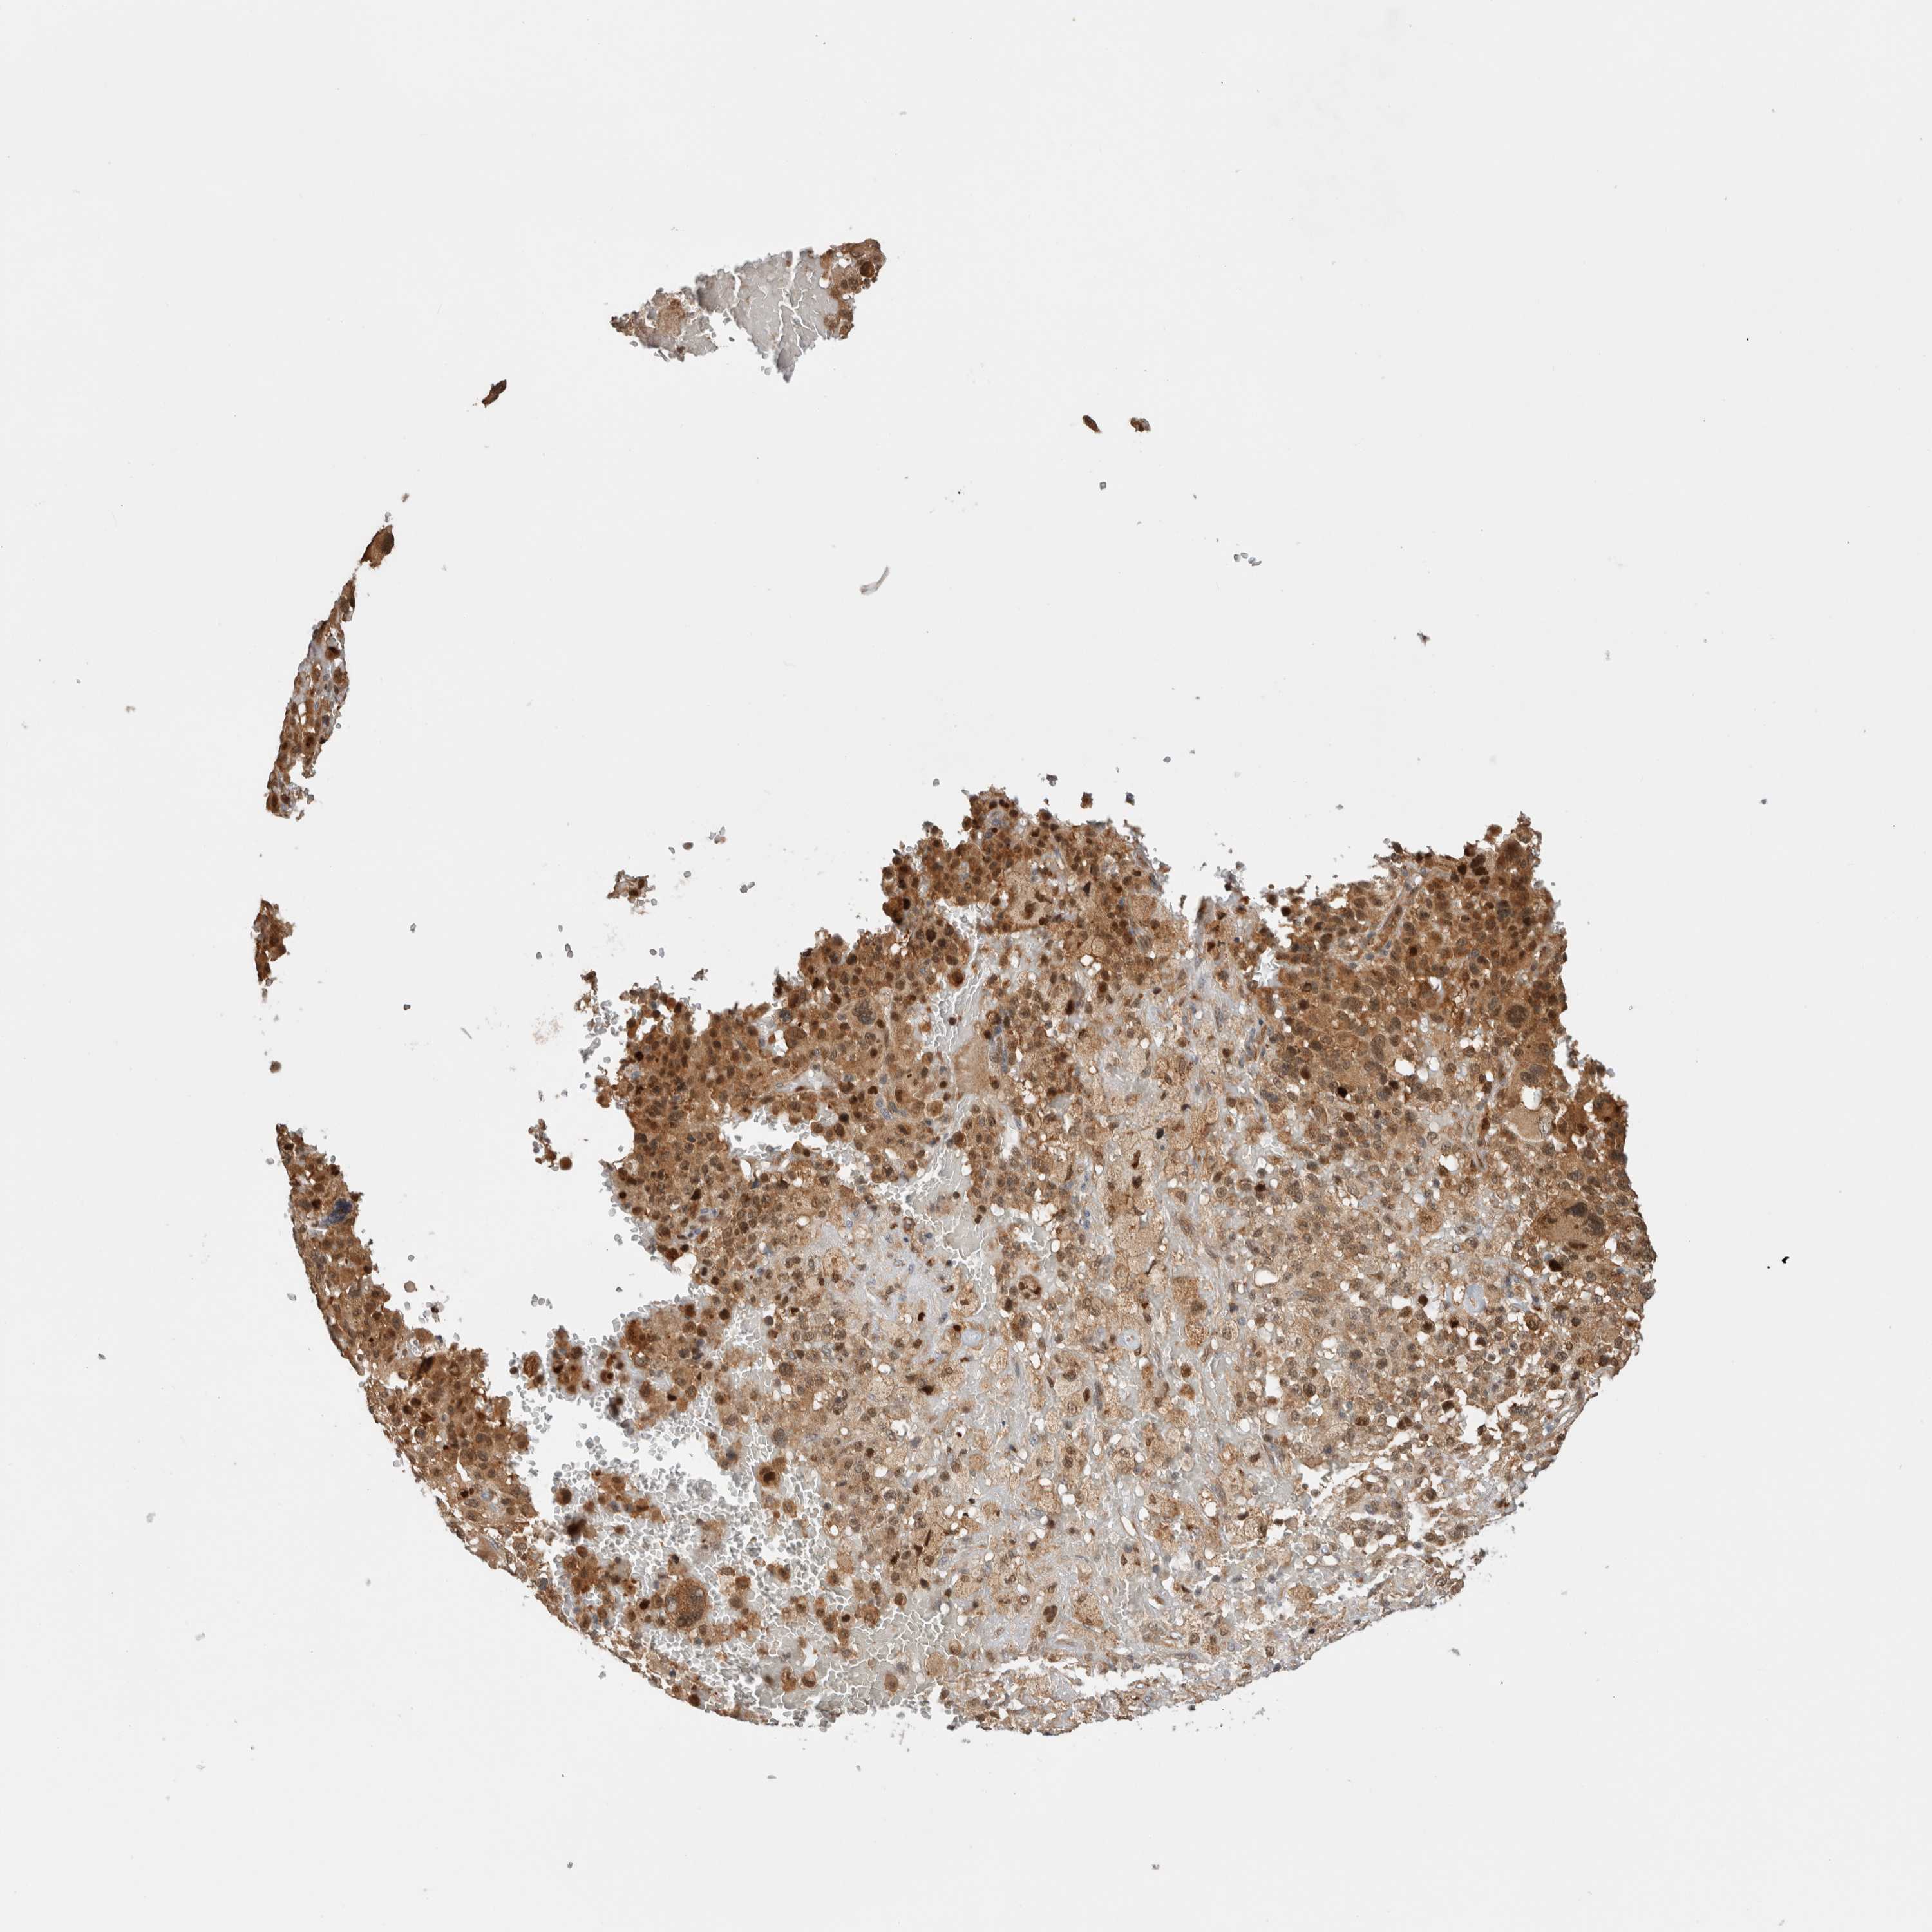

MELANOMA - Protein expressioni

A mouse-over function shows sample information and annotation data. Click on an image to view it in a full screen mode. Samples can be filtered based on level of antibody staining by selecting one or several of the following categories: high, medium, low and not detected. The assay and annotation is described here.

Note that samples used for immunohistochemistry by the Human Protein Atlas do not correspond to samples in the TCGA dataset.

Antibody stainingi

Antibody staining in the annotated cell types in the current human tissue is reported as not detected, low, medium, or high, based on conventional immunohistochemistry profiling in selected tissues. This score is based on the combination of the staining intensity and fraction of stained cells.

Each image is clickable and will lead to virtual microscopy that enables deeper exploration of all samples and also displays staining intensity scores, fraction scores and subcellular localization as well as patient and tissue information for each sample.

Antibody HPA024046

Antibody HPA024503

Antibody HPA024772

Staining

High

Medium

Low

Not detected

Intensity

Strong

Moderate

Weak

Negative

Quantity

>75%

75%-25%

<25%

None

Location

Nuclear

Cytoplasmic/membranous

Cytoplasmic/membranous,nuclear

Malignant melanoma, NOS

Malignant melanoma, Metastatic site